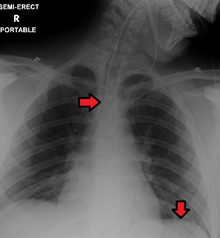

Great care must be taken to ensure that the tube has not passed through the larynx into the trachea and down into the bronchi. To ensure proper placement it is recommended (though not unequivocally confirmed) that injection of air into the tube be performed,[3] if the air is heard in the stomach with a stethoscope, then the tube is in the correct position. The use of air injected in to the stomach is no longer a satisfactory, safe way of confirming tube position in the UK.[4] There have been instances where this 'confirmation' technique was used and the NGT was in the patients lungs leading to aspiration pneumonia and then death. Another more reliable method is to aspirate some fluid from the tube with a syringe. This fluid is then tested with pH paper (note not litmus paper) to determine the acidity of the fluid. If the pH is 4 or below then the tube is in the correct position. If this is not possible then correct verification of tube position is obtained with an X-ray of the chest/abdomen. This is the most reliable means of ensuring proper placement of an NG tube.[5] The use of a chest x-ray to confirm position is the expected standard in the UK, with Dr/ physician review and confirmation. Future techniques may include measuring the concentration of enzymes such as trypsin, pepsin, and bilirubin to confirm the correct placement of the NG tube. As enzyme testing becomes more practical, allowing measurements to be taken quickly and cheaply at the bedside, this technique may be used in combination with pH testing as an effective, less harmful replacement of X-ray confirmation.[6] If the tube is to remain in place then a tube position check is recommended before each feed and at least once per day.